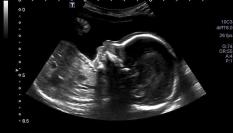

El divertido vídeo de una ecografía que muestra la pelea de dos gemelas

¡En la semana 16 de embarazo!

Menuda sorpresa se llevaron estos padres en la última ecografía de sus bebés. Iban a ver cómo evolucionaban las gemelas y se las encontraron peleando.

“Parecía que estaban boxeando”, contó al China Mail el padre, que explicó también que el momento fue especialmente emocionante porque la ecografía se hizo en la semana 16 de embarazo.

“Nos emocionó mucho. Las bebés eran tan pequeñas... y ya sabían cómo cuidar la una de la otra. Creo que vivirán en armonía cuando crezcan”, dijo el progenitor que cree ver un abrazo al final del enfrentamiento.